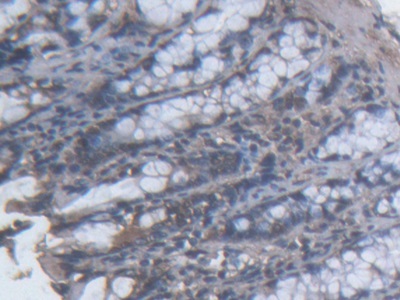

IHC (Immunohistchemistry)

(At 1/100 staining Mouse colorectal tissue by IHC-P. The sample was formaldehyde fixed and a heat mediated antigen retrieval step in citrate buffer was performed. The sample was then blocked and incubated with the primary antibody at 4 degree C overnight. An HRP conjugated anti-Rabbit antibody was used as the secondary antibody.)